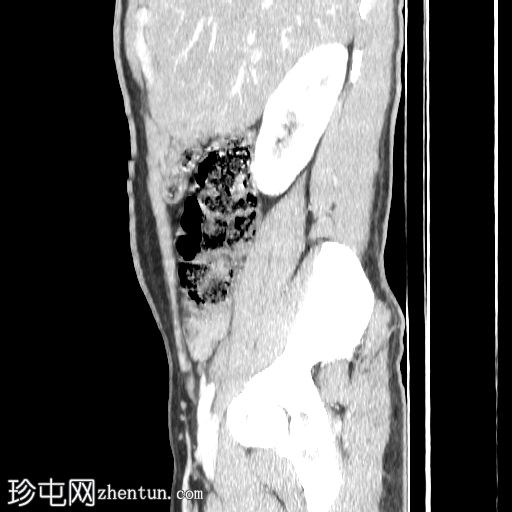

CT肾血管造影显示一条起源于左肾下段的副肾静脉,该静脉环绕主动脉走行,并接受来自腰静脉的属支,走行于主动脉后方,最终汇入下腔静脉。

双侧肾脏集合系统重复,分为上极和下极两部分。右侧输尿管在中段汇合,而左侧输尿管在进入膀胱前仍部分分离,符合双侧部分输尿管重复畸形(双分输尿管)。

本病例展示了一条环绕主动脉的副左肾静脉,其走行于主动脉后方并汇入下腔静脉,而右肾静脉解剖结构正常。

双侧重复肾盂输尿管系统,上下极部分明显。右侧重复的输尿管在中段汇合,而左侧输尿管在进入膀胱前仍部分分离,符合双侧部分输尿管重复畸形(双分输尿管)。双肾大小、位置、轮廓和实质厚度均正常,造影剂浓度和排泄功能正常。未见肾结石、肾积水或局灶性肾脏病变。